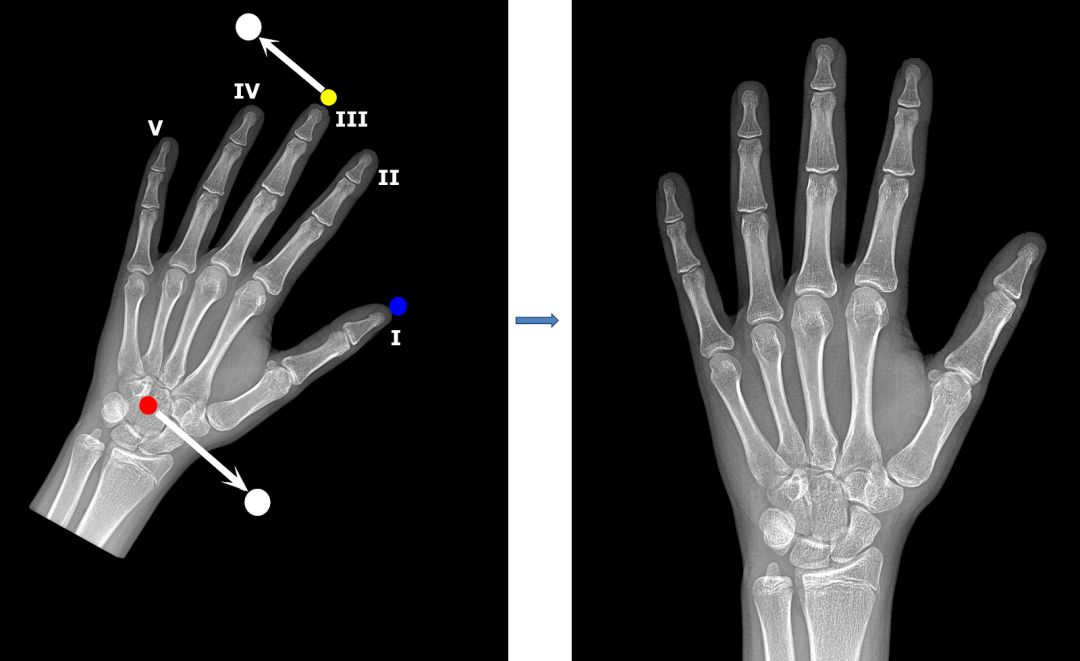

骨龄反映了你的年龄:骨龄评估 骨龄,基本上就是指你的骨头看起来多大了。随着孩子的成长,他的骨骼也在逐渐成长。这就意味着你可以通过观察儿童的骨骼,根据具备此类骨骼的儿童的平均年龄来了解这个孩子多大了。这时候你可能会想这是不是一篇考古学方面的文章:毕竟活着的小孩应该并不怎么拍 X 光。 这么想是对的,但是也不对。正常发育的话,儿童的骨龄应该在生理年龄(日历年龄)的上下 10% 区间内波动。但也有例外,例如,孩子青春期的生长突增可能会影响骨龄。因此,如果骨龄比生理年龄大几年的话,该儿童就会提前停止生长,而如果骨骼比较「年轻」的话,则可能会出现延迟的生长突增。此外,在给定身高和骨龄的情况下,你可以准确预测这个孩子的成年身高,这也可以派上一些用场:如果你的孩子喜欢篮球,你可能想知道他未来身高能否超过 7 英尺。 还有一些例外情况:骨龄和生理年龄严重不匹配是预示着身体出现问题,如成长障碍和内分泌问题等。骨龄只能告诉医生患者在特定时间时骨骼的相对成熟度,还要和其他临床指标结合才能区分出是正常生长还是生长相对提前或迟缓。连续的骨龄读数可以说明儿童的发育方向或治疗进展。通过评估骨龄,儿科医生可以诊断儿童发育过程中的内分泌和代谢紊乱问题,如骨发育不良或受营养、代谢或其他未知因素影响的生长缺陷,这可能会损害骨骺或骨质成熟。在这种生长迟缓情况下,骨龄和身高可能会有相同程度的延迟,但是经过治疗,此类儿童仍可达到正常成年人的身高。 综上所述,儿科医生常常会用 X 光照射儿童手部来评估其骨龄……所以自动化是一个很大的问题。 读手骨:从手掌和手腕评估骨龄 骨骼成熟度主要是通过骨骺中次级骨化中心的发育和骨化程度来评估的。几十年来,评估骨骼成熟度通常是根据对手骨和手腕的骨骼发育情况进行可视化评估来进行的。以下是放射科医生在查看手部 X 光片时看到的内容:

现在评估骨龄的两种最常用的技术是 Greulich-Pyle 法和 Tanner-Whitehouse(TW2)法。这两种方法都是根据成熟度指标,用左手手掌和手腕的放射图像评估骨骼成熟度,即管状骨的骨骺从骨化的最早阶段到它们和骨干融合的过程中放射影像呈现出的变化,或者是扁骨在变成成年人骨骼形状之前在放射影像上呈现出来的变化……别担心,我们在此之前也没听过这些。我们将这一过程展示在下图中:

如你所见,放射图像的质量和对比度有了显著的提升。你可以到这里停止预处理,用我们的预处理方法和标准技术(如缩放和旋转)来增强训练集,然后训练一个标准的卷积神经网络用于分类或回归。我们试了这种方法,尽管结果不如我们的最终模型,但是也很令人满意。 之前的 GP 和 TW 方法关注的是手骨的特定部位(包括指骨、掌骨和腕骨)。我们决定试着用这些信息,针对几个解析度较高的特定区域分别训练模型,再评估和比较它们的性能。为了正确定位这些区域,我们要将所有图的大小和位置转换成一样的,也就是说将它们放在相同的坐标空间中,该过程通常被称为图像配准(image registration)。 预处理 II:基于特征点进行图像配准 我们的图像配准策略很简单:检测手骨中几个特征点的坐标,然后计算仿射变换参数(缩放、旋转、平移和反射),使图像与标准位置一致。 为了创建特征点模型的训练集,我们用 VGG 图像注释器(VIA)手动标注了 800 张放射影像。我们选择了三个特征点:第三根手指远端指骨的顶端,拇指远端指骨的顶端以及头状骨的中心。我们将特征点的像素坐标作为回归模型的训练目标。 再说一次,特征点模型是受一系列 VGG 族模型启发、通过深度卷积神经网络实现的回归模型。VGG 模块由两个带有指数线性单元激活、批归一化和最大池化的卷积层组成。下图是其架构:

为了提升泛化性能,我们对输入应用了包括旋转、平移和缩放在内的标准增强。模型输出 6 个坐标,即 3 个特征点中每个特征点有 2 个坐标。 找到特征点后,我们就可以计算所有放射影像的仿射变换(缩放、旋转、平移)。我们的目标是在保持图像纵横比的情况下,将其调整到统一的位置: 1. 中指顶端水平对齐,在图像上边缘以下约 100 个像素处。 2. 头状骨水平对齐,在图像下边缘以上约 480 个像素处。 通常用左手的放射影像评估骨龄,但有时候数据集中的图像会呈镜像。为了检测这些图像并对其进行适当调整,我们使用拇指作为特征点。 来看一个图像配准模型起作用的例子。如你所见,手骨成功地旋转到我们希望的标准位置了: